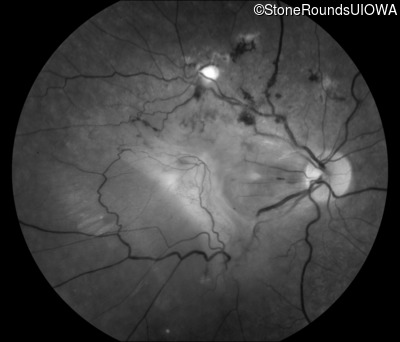

Fundus Photography - Right - 20/400 sc

Exemplar